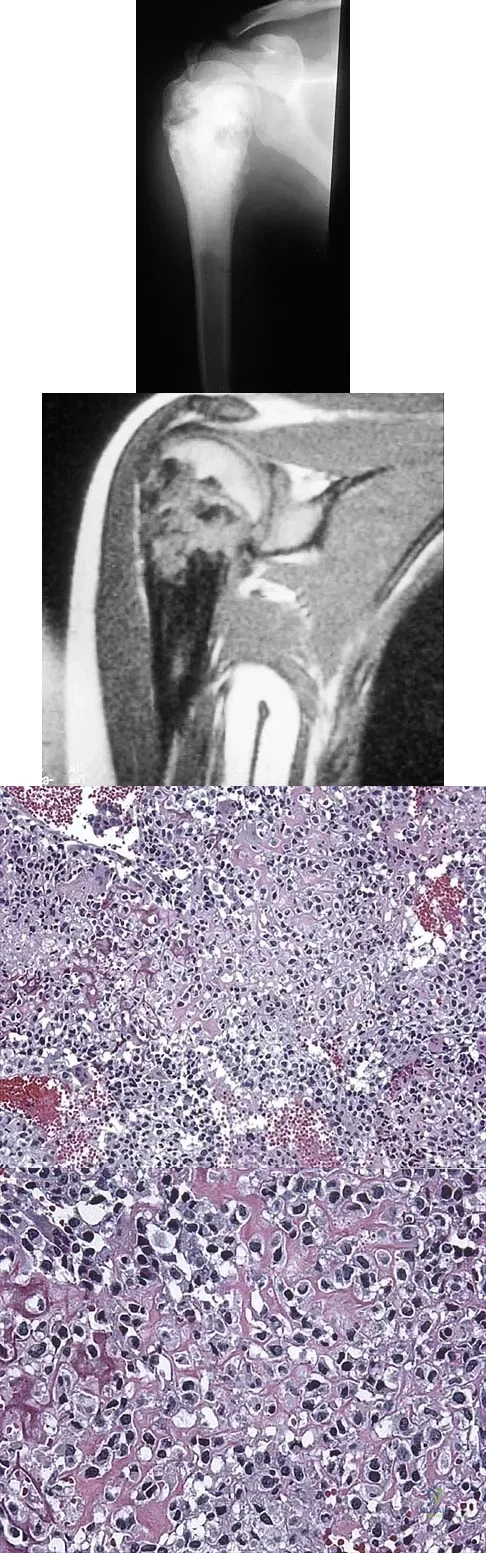

A 13-year-old girl has had a firm mass and pain in her right shoulder for the past several weeks. She denies any history of trauma. A radiograph and MRI scan are shown in Figures 31a and 31b. Biopsy specimens are shown in Figures 31c and 31d. What is the most likely diagnosis?

Explanation